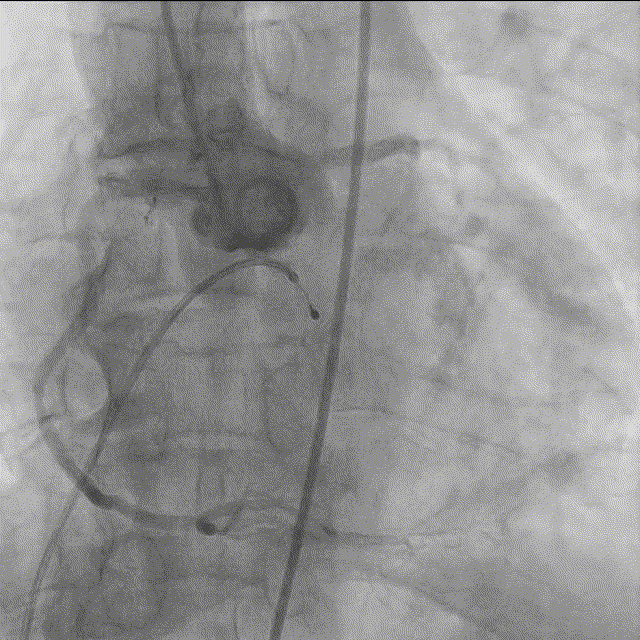

4. 右窦中心投照体位行主动脉根部造影;

5. AL2导管配合直头超滑导丝跨瓣;

6. 20mm球囊预扩张;

7. 23mm Silara-Valve瓣膜过弓和跨瓣;

8. 23mm Silara - Valve瓣膜左心室初步释放,瓣膜功能良好(不需要左心室快速起搏);

9. Silara - Valve提拉至瓣环水平,精准定位瓣膜,造影剂显示瓣膜功能良好,完成固化;

10. 最终造影瓣膜位置理想,无返流。